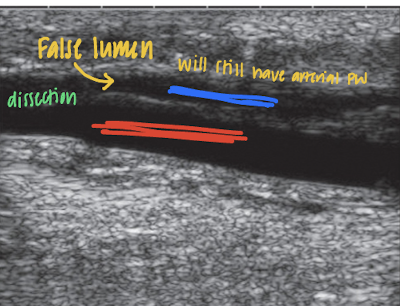

dissections

intimal flaps